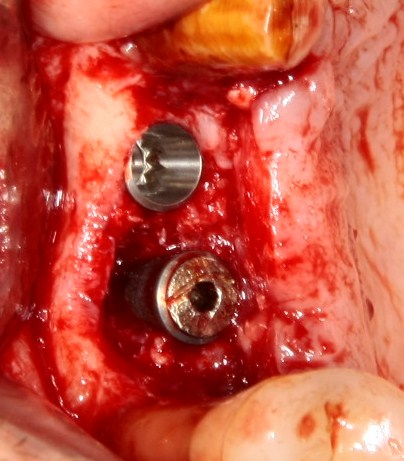

Например, в следующей ситуации:

Оставить так, как есть — это значит, сильно рисковать имплантом и объемом альвеолярного гребня — фактически, большая часть импланта пятого зуба «висит в воздухе». Поэтому получившуюся костную полость мы заполняем аутокостной стружкой в смеси с Bioss и закрываем коллагеновой мембраной BioGide:

При необходимости, мембрану можно фиксировать пинами.

Через три месяца результат:

можно ставить формирователи и заканчивать лечение: